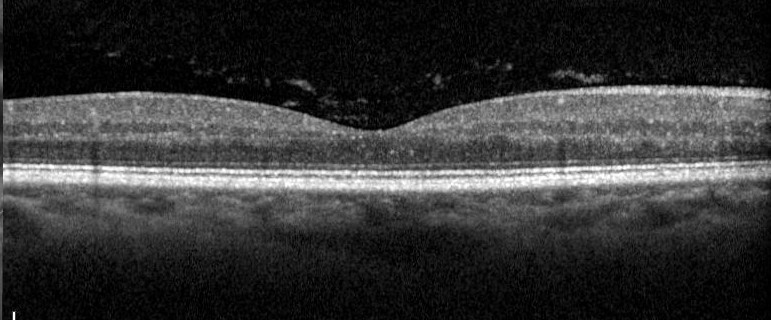

Objectively, floaters can be observed on a slit lamp exam. Dr. Zhu said to create a thin, high-intensity beam, hold it at an angle, and focus on the anterior vitreous just behind the lens. If the floaters are deeper in the vitreous cavity, they can be viewed with a mid-vitreous lens. Sometimes they are also visible as a clump or Weiss ring floating over the retina on the dilated fundus exam with a 20 D lens. They can also be reviewed with an OCT macula en face view, represented as a gray or black shadow over the central retina.